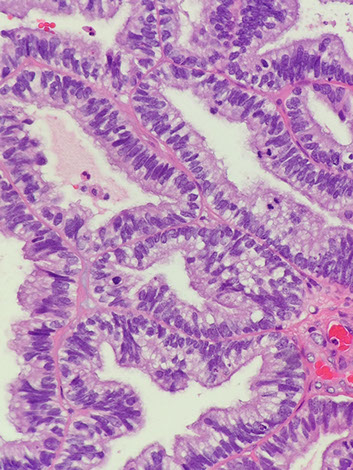

Choroid Plexus Papilloma

WHO grade I

Tumor closely resembles normal choroid plexus, except it forms a mass

- can see hydrocephalus due to CSF overproduction or obstruction, although generally behaves in a benign manner

85% seen in kids (~10 yo), intraventricular (lateral ventricles) tumor

Micro: Benign papillary tumor

- distinguish from normal choroid plexus by closely inspecting the lining epithelium

-- normal choroid plexus is lined by taller columnar epithlium which is smooth, but lacks the undulating surface of normal choroid plexus epithelium which is smooth and lacks the undulating surface of normal choroid plexus

- there should be no signoficant atypia and mits should be absent or rare

IHC: (+) CAM5.2 (94%), transthyretin (89%), GFAP, Kir71